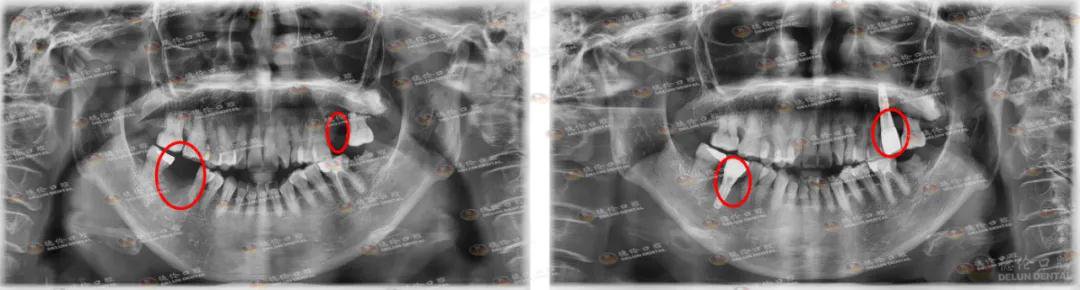

每一面锦旗背后, 都是一个个充满温情的故事。据悉,林阿姨左上颌6、右下颌6患有龋齿,龋齿由浅入深,由小到大,从没有症状到疼痛难熬,越来越严重,林阿姨直到后面痛到顶不住才到医院就诊,那两颗龋齿已经没救了,需要拔除处理。

2018年,王医生采用数字化种植技术为林阿姨种了两颗牙。距离林阿姨种完牙过去两年,为何林阿姨会选择这个时间点来送锦旗呢?

林阿姨术前(左)术后(右)牙片